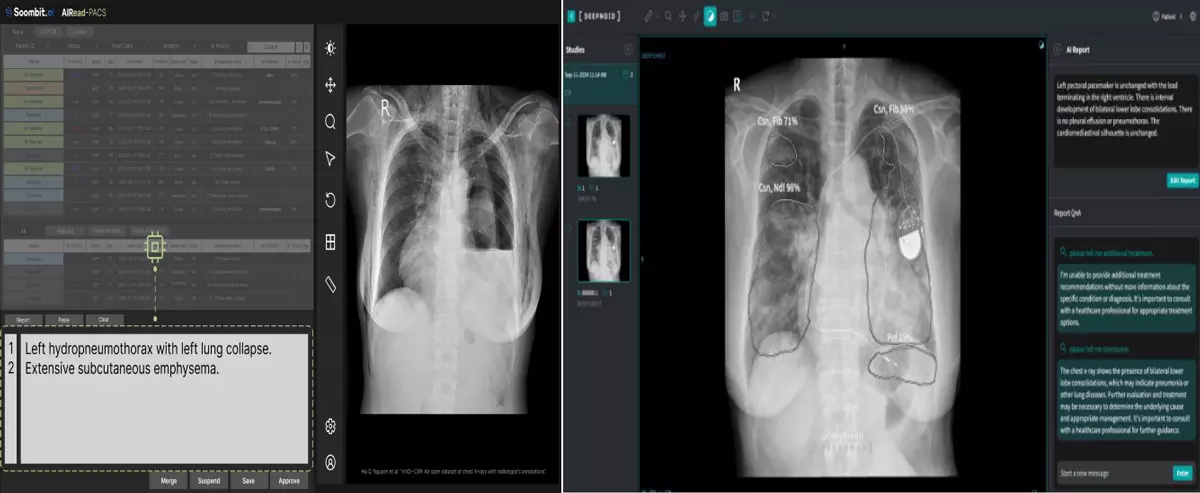

1일 업계에 따르면 딥노이드와 숨빗AI가 각각 개발한 흉부 엑스레이 판독문 자동 생성 솔루션이 식약처 품목 허가 최종 단계에 접어들었다. 이르면 이달 중 국내 1호 타이틀이 결정될 전망이다.

딥노이드는 지난해 11월 자사 M4CXR 임상시험을 마치고 식약처 품목 허가 결정을 기다리고 있다. M4CXR은 비전 트랜스포머와 거대언어모델 기술을 결합해 이미지와 텍스트를 동시에 분석하며 1000만 건 이상의 판독 소견서 데이터를 학습해 41종의 병변과 80개 이상의 질환을 분석한다. 부산대학교병원 연구팀 성능 평가 결과 M4CXR의 임상적으로 유의미한 소견 정확도는 85%로 나타났다. 특히 응급실 환경에서도 87.6%의 정확도를 보였으며 판독 소견서 초안 작성에는 평균 3.4초가 소요됐다. 딥노이드 측은 상반기 내 정식 출시를 목표하고 있다.

숨빗AI AIRead-CXR 역시 식약처 품목 허가 마지막 단계에 진입했다. AIRead-CXR은 흉부 엑스레이에서 감지되는 다양한 소견을 기반으로 개인 맞춤형 초안 판독문을 생성하는 소프트웨어다. 의사의 주관적 판단 개입을 배제하기 위해 흉부 영상만을 입력값으로 사용하며 외부 모델이 아닌 자체 개발 AI 모델을 기반으로 일관된 결과물을 도출하는 것이 강점이다.

자체 연구 결과에 따르면 AIRead-CXR을 활용한 영상의학과 의사는 판독 소요 시간이 평균 42% 단축되고 판독 품질은 6% 향상된 것으로 나타났다. 숨빗AI 관계자는 "현재 식약처 심사는 마지막 단계에 있으며 오는 4월 정식 출시를 목표로 의료진이 더 정확하고 신속하게 판독할 수 있는 환경을 구축해 현장의 여러 문제점을 해결하는 데 집중하고 있다"고 설명했다.